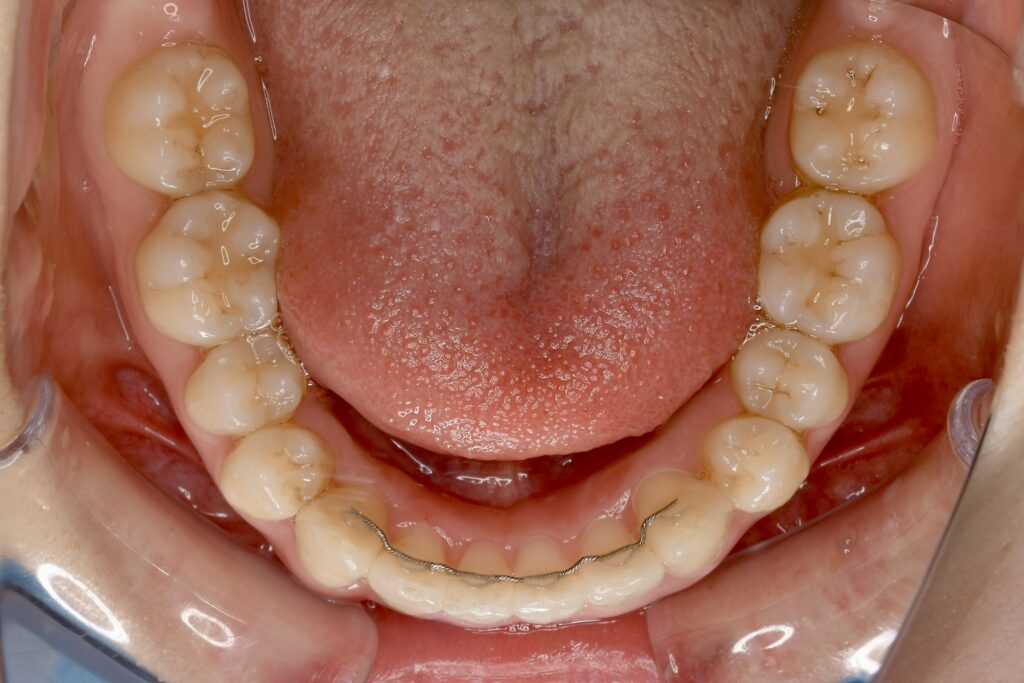

21歳 女性 治療期間:1年1ヶ月

叢生(ガタガタ)

マウスピース矯正装置(インビザライン)

BEFORE

AFTER

主訴

周りの人の歯並びが綺麗で自分の歯並びを治したくなってきた。

診断名・主な症状

叢生

治療内容

上下とも歯並びの横幅を広げながら、でこぼこを解消しました。

マウスピース矯正(インビザライン)

抜歯あり(智歯抜歯)

治療期間

1年1ヶ月

通院回数

10回

費用

85万円程度(税別)

リスク・副作用

痛み、歯肉退縮、歯根吸収、抜歯に伴う出血や腫れが生じることがあります。